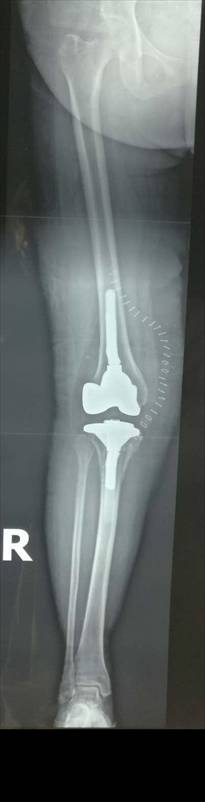

术前术后对比

全膝关节翻修术

全髋关节翻修术